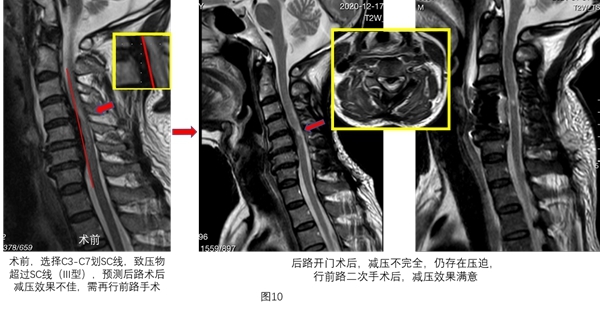

作用3:指导手术入路,确定是否需再行前路手术及其减压节段。

关于手术入路的选择,一些节段受压严重,后路手术无法取得满意的减压效果,而前路风险较大,需要先行后路手术,再行前路手术,根据SC线及其分型,可精准预测是否需再行前路手术及手术减压节段。

对于压迫严重的节段(SC线III型),即使扩大减压范围也无法获得满意的减压效果的,需要对该节段进行前路二次手术,术后可获得满意的减压效果(图10~图11)。